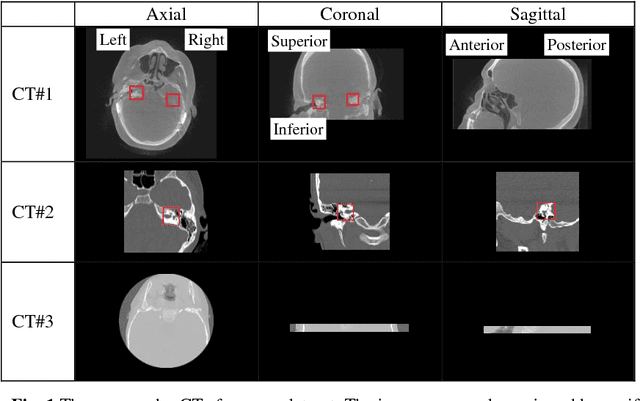

Abstract:Cochlear implants (CIs) are neural prosthetics which are used to treat patients with hearing loss. CIs use an array of electrodes which are surgically inserted into the cochlea to stimulate the auditory nerve endings. After surgery, CIs need to be programmed. Studies have shown that the spatial relationship between the intra-cochlear anatomy and electrodes derived from medical images can guide CI programming and lead to significant improvement in hearing outcomes. However, clinical head CT images are usually obtained from scanners of different brands with different protocols. The field of view thus varies greatly and visual inspection is needed to document their content prior to applying algorithms for electrode localization and intra-cochlear anatomy segmentation. In this work, to determine the presence/absence of inner ears and to accurately localize them in head CTs, we use a volume-to-volume convolutional neural network which can be trained end-to-end to map a raw CT volume to probability maps which indicate inner ear positions. We incorporate a false positive suppression strategy in training and apply a shape-based constraint. We achieve a labeling accuracy of 98.59% and a localization error of 2.45mm. The localization error is significantly smaller than a random forest-based approach that has been proposed recently to perform the same task.